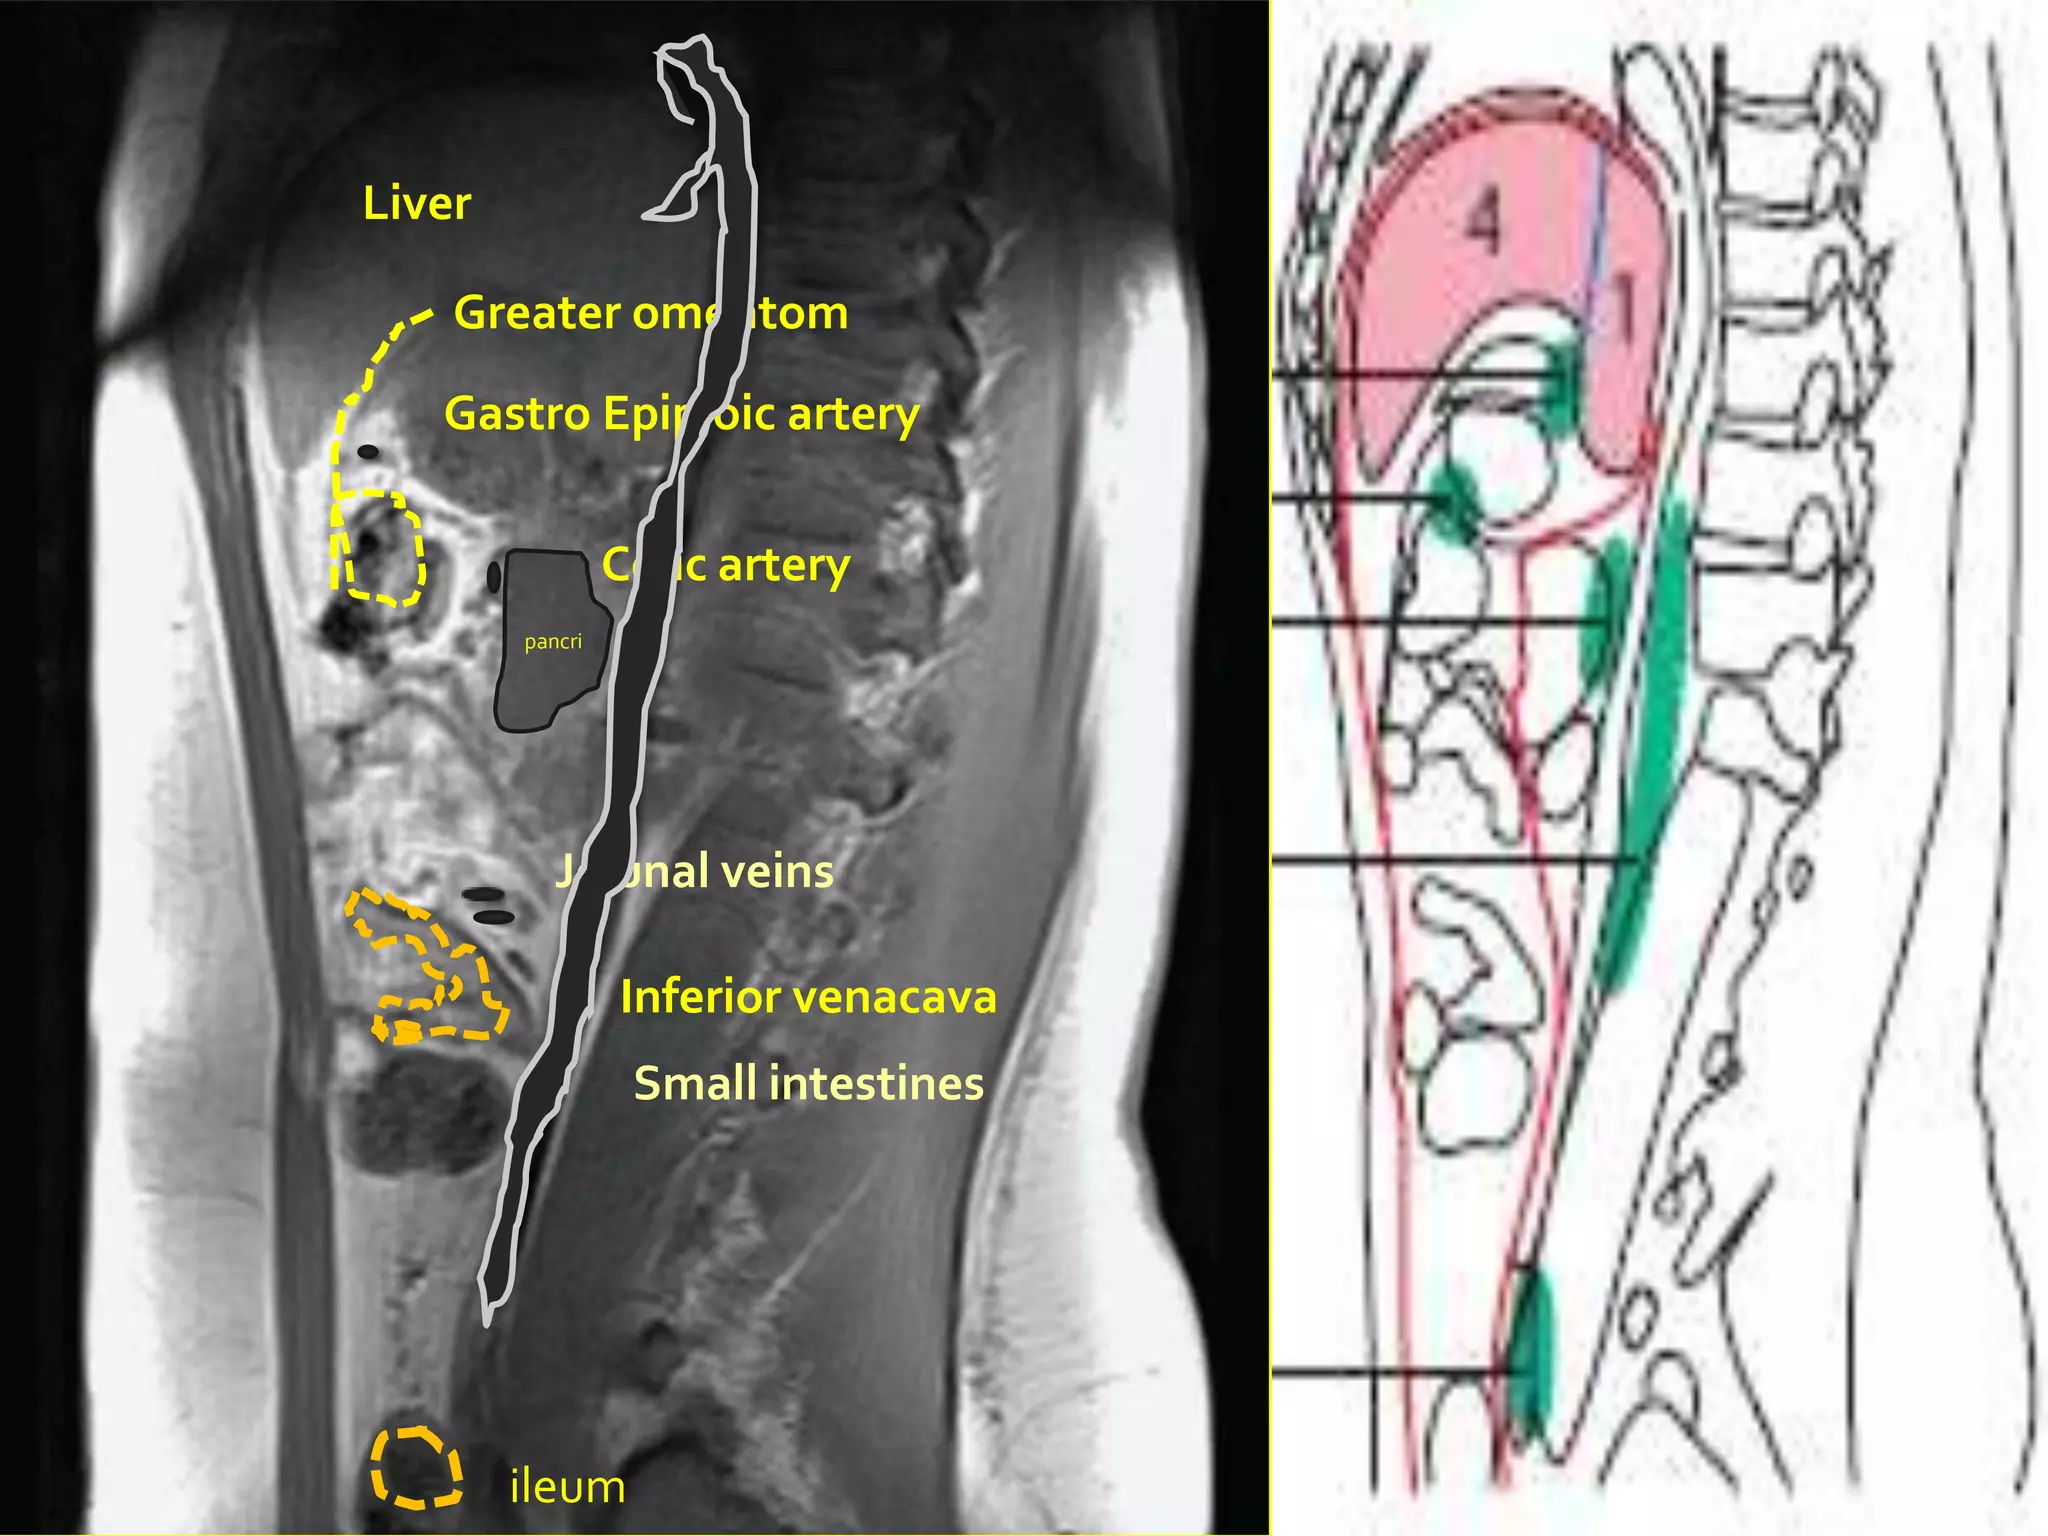

Liver

Greater omentom

Gastro Epiploic artery

Colic artery

pancri

Jejunal veins

Inferior venacava

Small intestines

ileum